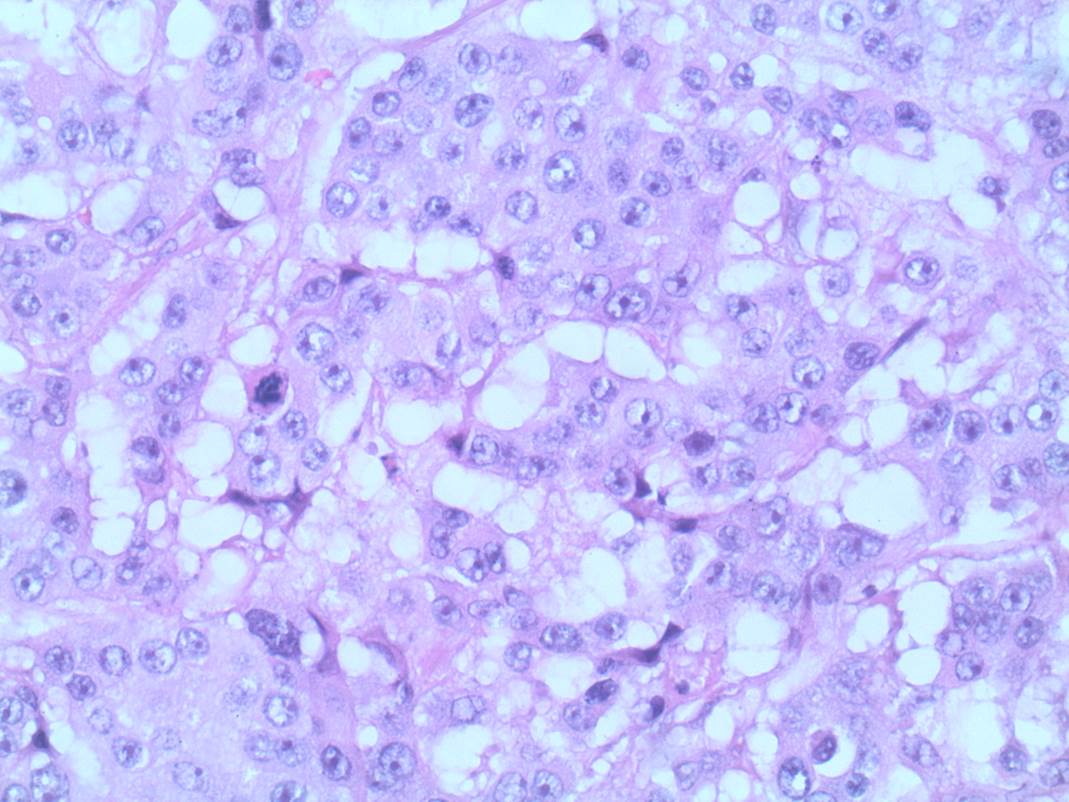

In early breast cancer, this is primarily based on the size of the invasive carcinoma and the status of the associated axillary lymph nodes. For patients with clinically node negative disease, sentinel lymph node biopsies are often used to assess the nodal status. In some cases, often those patients with higher risk tumours, an intraoperative “frozen section” will be performed proceeding to axillary lymph node dissection in the same procedure if positive (Figure 3 –metastatic carcinoma in a lymph node). In others, the sentinel nodes will be assessed post-operatively with the definitive breast excision specimens. The most recent international staging system (AJCC 8th Edition) also incorporates grade, hormone and HER2 receptor status to assign a prognostic stage, highlighting the significant impact of targeted therapies on outcome.

This image depicts metastatic carcinoma in a lymph node. Professional medical imaging for clinical reference and educational purposes. [umbracoNodeId=9800]

Figure 3: Metastatic carcinoma in a lymph node